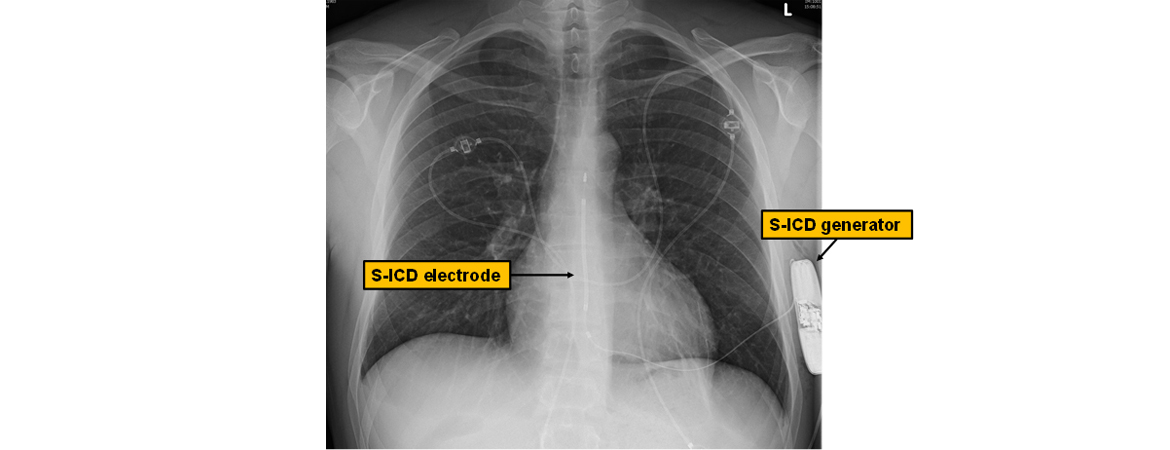

Tardu Özkartal, Alexander Breitenstein, Ardan M. Saguner, Devdas T. Inderbitzin, Markus J. Wilhelm, Stefano Benussi, Francesco Maisano, Thomas F. Lüscher, Frank Ruschitzka, Jan Steffel (Author)